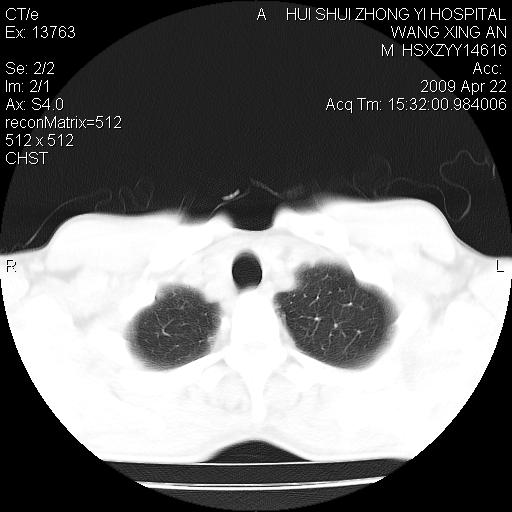

标题: CT19534:患者男、46岁咳嗽、胸痛半月。 [打印本页]

标题: CT19534:患者男、46岁咳嗽、胸痛半月。

考虑---右肺中心型肺癌继发下叶不张,少量胸水。

支持右侧中央型肺ca并右下肺不张、右侧胸腔少量积液。

1、右下肺中央型肺癌并右肺转移,右肺下叶不张。(肿块围绕右肺下叶支气管生长,致管腔闭塞右肺下叶不张;右肺有结节影)。

2、右侧胸腔积液。

3、右中上肺陈旧性肺结核(右肺见纤维化病灶及点状钙化)。

1)右肺中间段支气管癌并右肺下叶肺不张。2)右肺上叶、两肺下叶背段感染性病变。3)右侧少量胸腔积液。